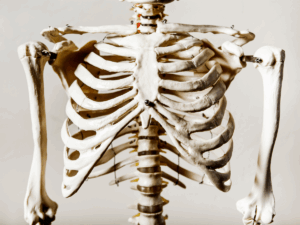

この時、横隔膜がしっかり動くことで深く安定した呼吸ができるようになります。

しかし、普段から呼吸が浅い人は息を吸う時にうまく肋骨を広げられず、代わりに肩を持ち上げるような呼吸パターンが染みついてしまっています。

肩を持ち上げるような呼吸(胸式呼吸)が習慣化していると、首や肩周りの筋肉に負担がかかり、慢性的な肩こりや首こりの原因になります。